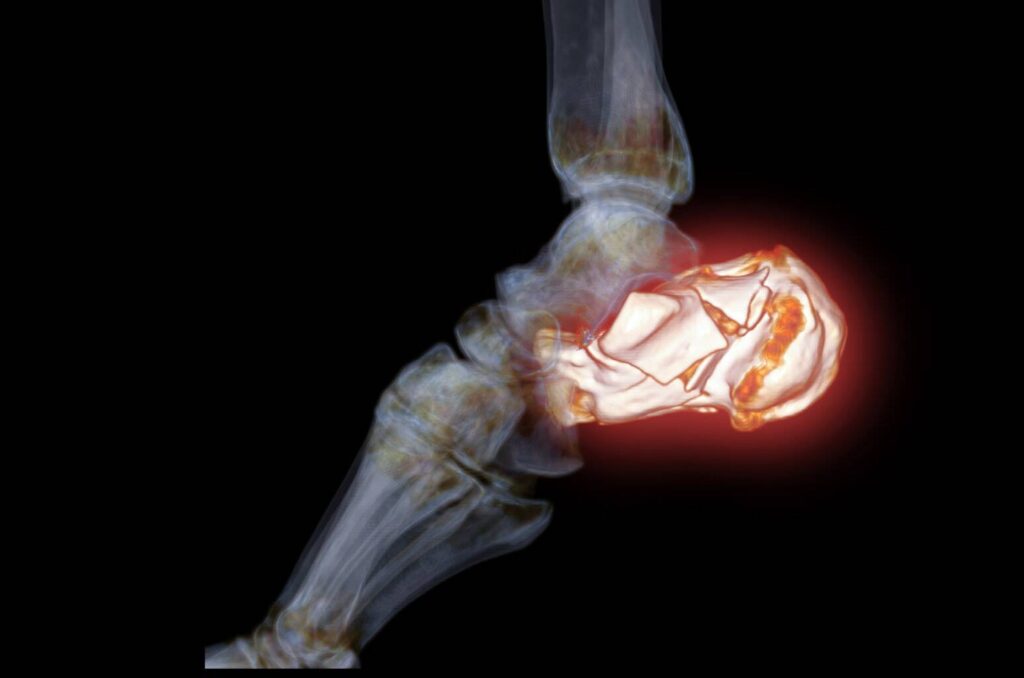

Ein CT Sprunggelenk-Scan ist ein medizinisches bildgebendes Verfahren, das Röntgenstrahlen und Computertechnologie verwendet, um Schnittbilder des Knöchelgelenks zu erstellen. Diese Bilder liefern detaillierte Informationen über die Knochen, Gelenke, Bänder, Sehnen und Weichteile im Knöchel. CT-Scans sind besonders nützlich zur Diagnose und Bewertung einer breiten Palette von Knöchelerkrankungen, einschließlich Frakturen, Verstauchungen, Arthritis und anderen muskuloskelettalen Problemen.

- Präzise Diagnose: CT Sprunggelenk-Scans bieten hohe Bildauflösung und 3D-Darstellungen, die detaillierte Einblicke in die Anatomie des Sprunggelenks ermöglichen. Dies führt zu einer präzisen Diagnose von Verletzungen und Erkrankungen.

- Identifikation von Frakturen: CT-Scans sind besonders wirksam bei der Identifizierung von Knochenbrüchen im Sprunggelenk, wobei Art und Schweregrad der Fraktur genau ermittelt werden können.